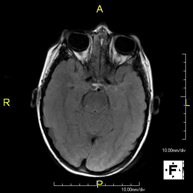

Magnetic Resonance Imaging

Skull MRI

This non-invasive diagnostic procedure uses an electromagnetic field and radio waves (from a transmitter and receiver) to acquire high-definition anatomical images of the skull. It is a radiation-free procedure. Sometimes paramagnetic contrast (gadolinium) must be used to complete the study.